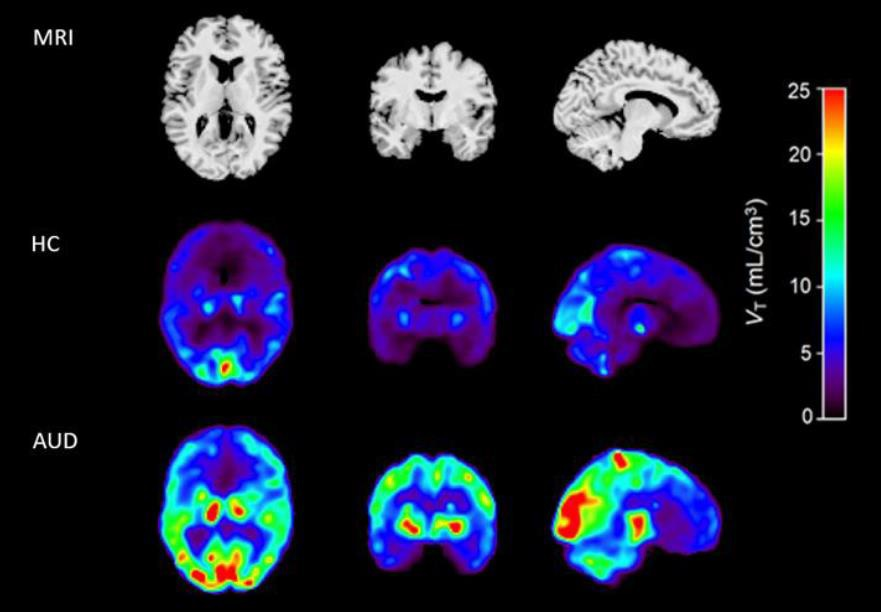

Functional MR image (right) shows activation, especially in left sensorimotor cortex, in response to the finger-tap task. The hemodynamic response function (HRF) charts (left) show average fMRI response to finger-tap event averaged over 19 trials for each healthy control subject (CTL) and each subject with alcohol use disorder (AUD). Arrows indicate main finding of slower HRF among AUD subjects, which significantly correlated with the number of lifetime drinks consumed. Image set courtesy of John Desmond, PhD, et al."Because the hemodynamic response is necessary for brain cells to be efficiently activated, the effects of alcohol consumption on the HRF could contribute to the behavioral and cognitive impairments associated with alcohol use disorder, and perhaps to difficulties in curbing drinking," the researchers concluded.